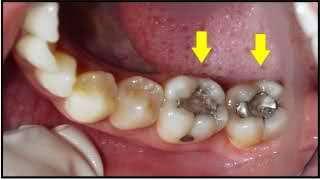

When their teeth decay we will fill them with metals that will kill their mind and steal their future.